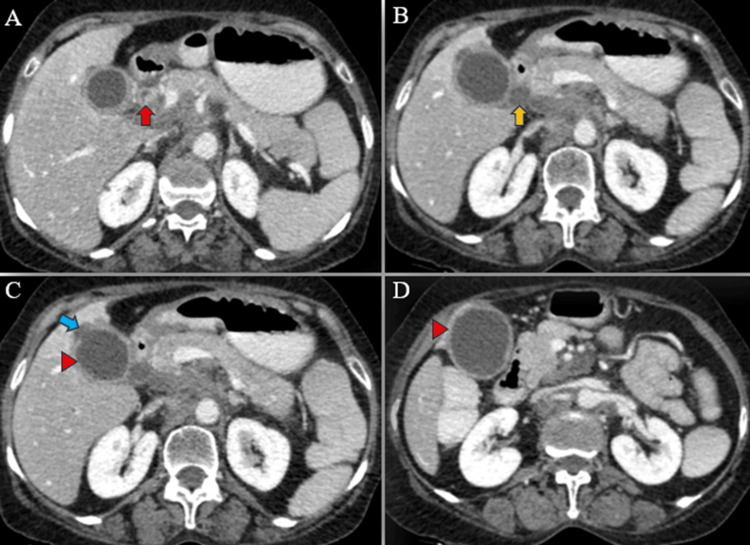

Magnetic resonance (MR) abdomen imaging with MR cholangiopancreatography (MRCP) revealed an overdistended gallbladder with circumferential wall thickening measuring 4 mm. Bile appeared hypointense on T2-weighted imaging (T2WI), indicative of sludge or thick material, with diffusion restriction on diffusion-weighted imaging (DWI) and low apparent diffusion coefficient (ADC) values. A 7 mm defect was noted in the body region, with T2 hyperintense pericholecystic fluid collection demonstrating diffusion restriction adjacent to the body. Mild dilatation of the IHBR was observed in both the right and left lobes. The CBD measured 8 mm in diameter, with narrowing of the mid-CBD due to circumferential wall thickening measuring 4 mm. The remainder of the CBD appeared normal in caliber (Figures 9–10).

Multiple enlarged lymph nodes were noted at various locations, including the porta hepatis, peripancreatic region adjacent to the pancreatic head, celiac region, aorto-caval region, pre-aortic, left para-aortic region, and retrocaval region (Figure 11). These lymph nodes exhibited T1WI hypointensity and T2WI heterogeneous hyperintensity, with central necrotic areas of variable sizes. Some lymph nodes demonstrated diffusion restriction on DWI and appeared coalescent. The pancreas appeared normal. Visualized lower lobes of both lungs exhibited well-defined T2WI hyperintense lesions ranging in size from 2 to 15 mm, with peripheral and subpleural distribution.

These findings were suggestive of a stricture in the mid-CBD, likely neoplastic (cholangiocarcinoma), resulting in proximal biliary obstructive dilatation. Additionally, the gallbladder exhibited changes consistent with empyema and contained perforation. Multiple metastatic lymph nodes were observed in the retroperitoneum and porta hepatis, along with multiple lung metastases.